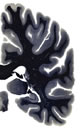

Hi-Resolution Sections · Cells (Nissl Staining) · Virtual Microscopy

Frontal sections (Nissl) from the Atlas Brain: Gallery Slice Single